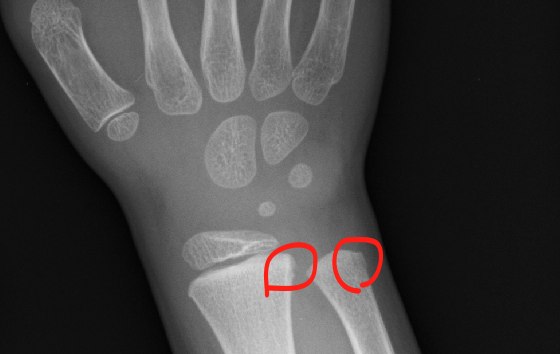

分かりにくいかもしれないが、レントゲンの写真をもらったので載せておこう。